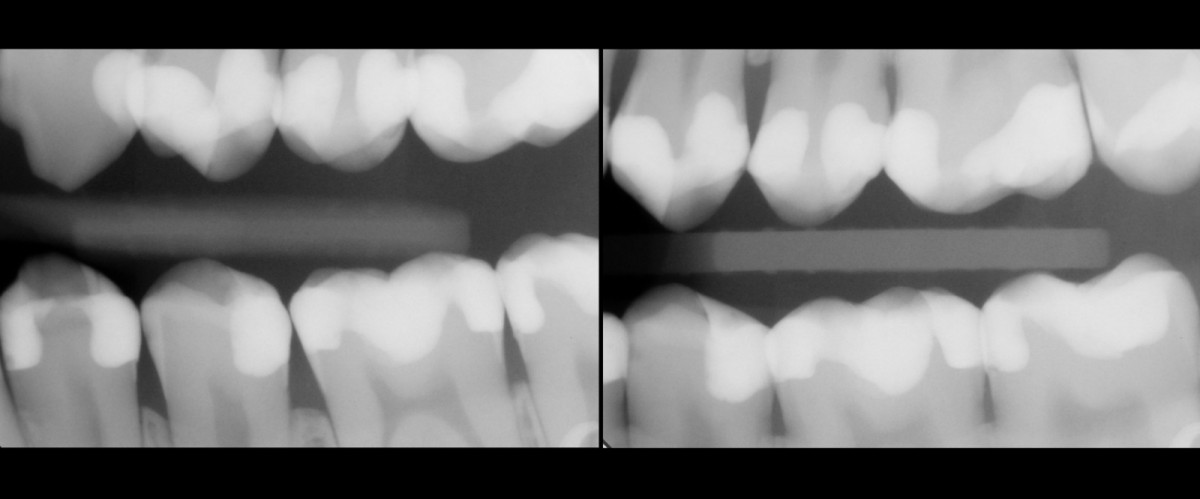

Clinical examination highlighted old direct restorations on 3.7 and 3.6, with irregular margins and initial signs of infiltration. Rx examination (orthopantomography and bitewings) revealed primary interproximal decays with dentinal involvement on 3.4, 3.5, 3.6 and 3.7. Vitality test was carried out and confirmed that all elements were vital.

Oral hygiene motivation was carried out, alongside with proper periodontal treatment (scaling, polishing) before taking initial photo (Fig.1). Initial rx bitewing of the quadrant (Fig.2).

Final rx bitewings (Fig.16).